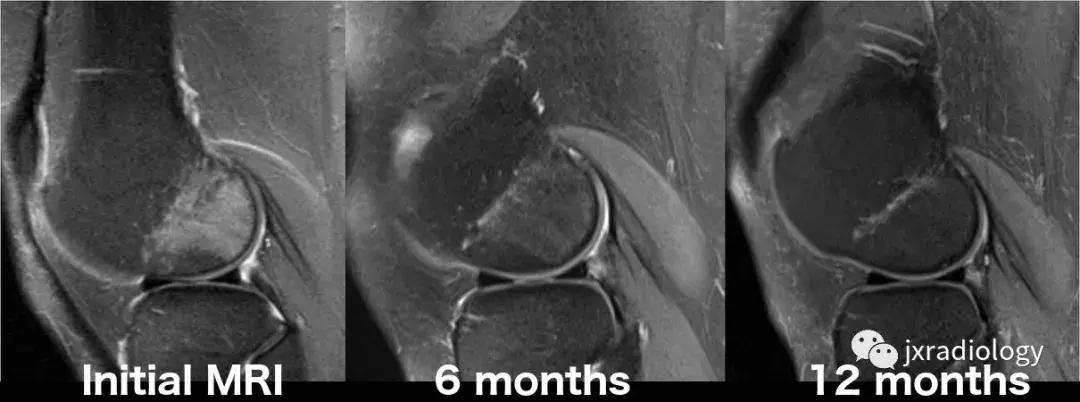

图25:短暂性骨髓水肿综合征(短暂性骨质疏松症):30岁女性急性膝部疼痛的矢状位FS-PDWI MR影像显示骨髓水肿,涉及非负重区域股骨外侧髁骨髓水肿在1年内几乎完全自发消退。短暂性骨髓水肿综合征是自限性病变,其表现为与MRI研究中的骨髓水肿证据相关的关节痛。 其病因仍不确定。